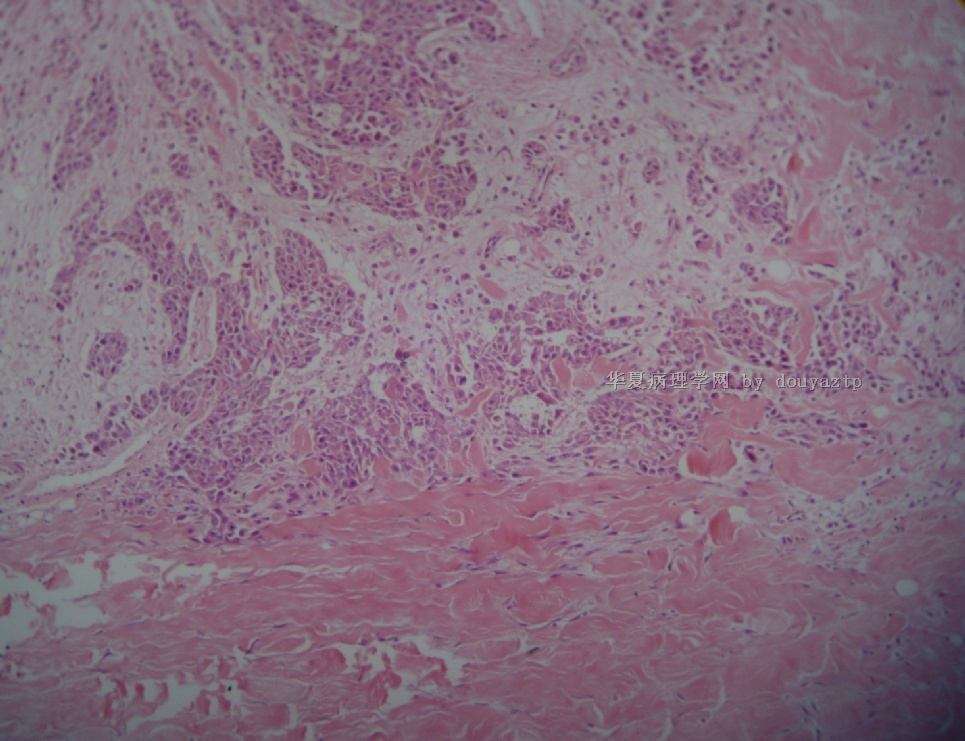

男性,37岁,大量血性胸水

这是几天后送检的病人右上腹壁的皮下包块。